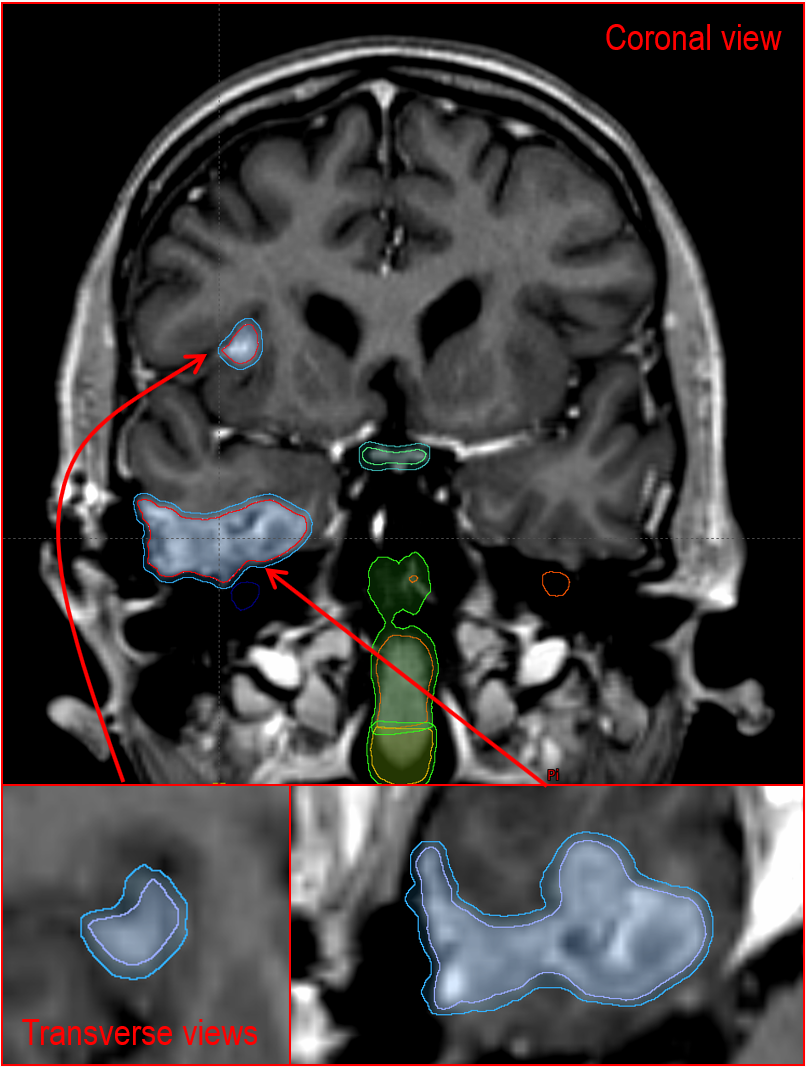

Hi Ethan we've done that a few times, it works very well.

See this attached case image.